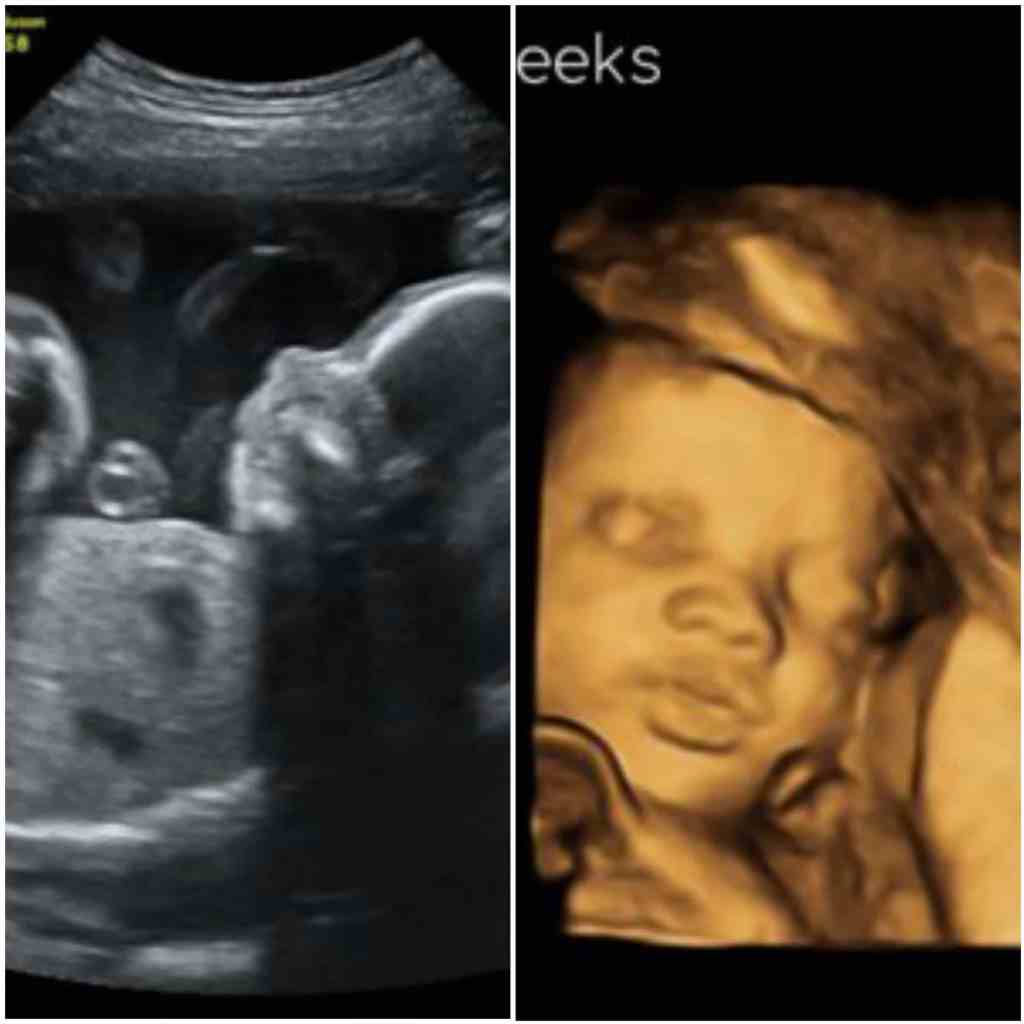

Si has elegido averiguar el sexo de tu bebé, lo más probable es que lo hagas a través de una ecografía. Por lo general, la ecografía se realiza a la mitad del embarazo. Se llama encuesta de anatomía fetal y se realiza para buscar anomalías fetales, no simplemente para averiguar el sexo de su bebé.

Dicho esto, más del 99% de las ecografías realizadas entre las semanas 18 y 20 harán la determinación correcta.4 Es sólo cuando se realiza antes de la semana 14 que la tasa de precisión puede caer significativamente.

Al determinar el sexo del feto en la ecografía, el ecografista buscará rasgos característicos conocidos como signos. En el caso de las niñas, hay dos signos que hay que buscar:

El signo de la hamburguesa: Es el nombre que recibe el aspecto de los labios y el clítoris en una ecografía. Si observas la imagen con detenimiento, verás que los labios vaginales tienen un aspecto similar al de un pan de hamburguesa, mientras que el clítoris se asemeja a la hamburguesa.

Signo sagital: Cada sexo tiene un signo sagital. Se obtiene observando una vista de perfil del feto (conocida como plano sagital de la línea media). En el extremo de la columna vertebral hay un punto que se llama muesca caudal. Si apunta hacia abajo con un ángulo de 10 grados, el feto es una niña.

Signos de la ecografía de un niño

Se podría pensar que los fetos masculinos son más fáciles de identificar que los femeninos, pero no siempre es así. Esto es especialmente cierto antes de la semana 14. Entre las semanas 18 y 20, la determinación de un bebé varón se basa en los siguientes signos:4

Signo sagital: Si la muesca caudal apunta hacia arriba con un ángulo superior a 30 grados, el feto es un niño. Si se encuentra en un punto intermedio, puede ser más difícil hacer una determinación definitiva.

Genitales masculinos: La presencia de genitales masculinos, incluidos los testículos, el escroto y el pene, suele observarse entre las semanas 18 y 20 y es un signo claro del sexo masculino.